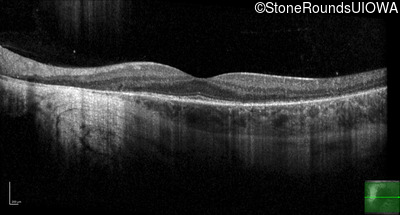

Age at visit: 32 years

This 30 year old man has had some difficulty seeing in dim light for the past few years.